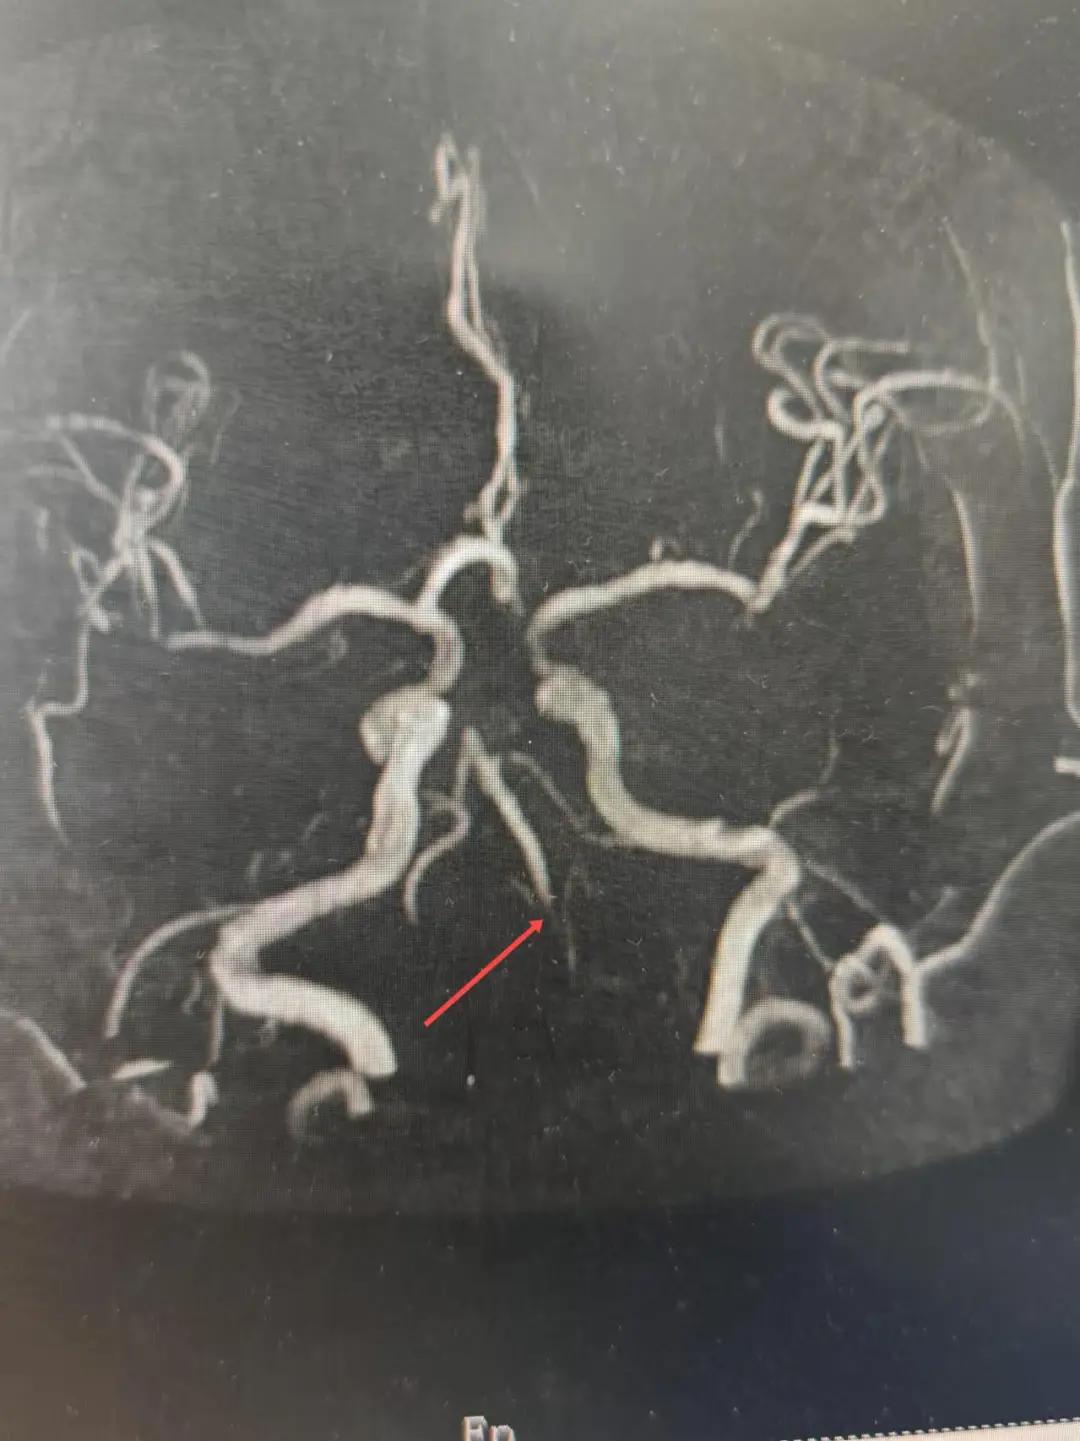

2024年12月19日,漯河市中醫(yī)院腦一科收治了一位79歲的女性患者?;颊咴谌朐呵?小時出現(xiàn)言語不利,右側(cè)肢體無力。腦一科醫(yī)師關(guān)卓杰接診后,全面評估患者病情,給予其靜脈溶栓,并急查頭顱MR。影像可見腦干、雙側(cè)枕葉、左側(cè)海馬旁回及丘腦新發(fā)梗塞灶,基底動脈閉塞?;颊咴陟o脈溶栓完畢后仍出現(xiàn)陣發(fā)性言語不利、右側(cè)肢體無力、頭暈。立即進行科室間會診,副主任醫(yī)師彭壯考慮患者出現(xiàn)上述癥狀與其基底動脈閉塞后顱內(nèi)動脈代償不良有較大關(guān)系,且基底動脈閉塞有較高的致死率與致殘率,建議行急診取栓,降低患者死亡及殘障風(fēng)險。家屬了解病情,知情同意后要求行介入治療。

磁共振MRA提示基底動脈閉塞